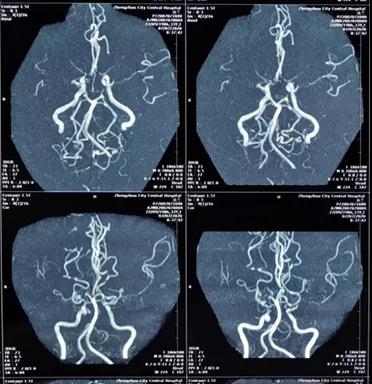

完善了术前准备后,贾映海教授和四川省人民医院黄光富教授强强联手,为赵女士实施了STA-MCA(颞浅动脉 - 大脑中动脉)搭桥术,用一根比头发丝儿还细的针线在直径仅仅1mm的血管上进行搭桥。